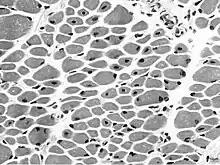

Muscle biopsy from the quadriceps taken at 3 months of age from a girl with X-linked centronuclear ("myotubular") myopathy due to a mutation in the myotubularin (MTM1) gene and extremely skewed X-inactivation (H&E stain, transverse section). Note marked variability in fibre size, moderate increase in connective tissue and numerous central nuclei.

On examination of muscle biopsy material, the nuclear material is located predominantly in the center of the muscle cells, and is described as having any "myotubular" or "centronuclear" appearance. In terms of describing the muscle biopsy itself, "myotubular" or "centronuclear" are almost synonymous, and both terms point to the similar cellular-appearance among MTM and CNM. Thus, pathologists and treating physicians use those terms almost interchangeably, although researchers and clinicians are increasingly distinguishing between those phrases.

In general, a clinical myopathy and a muscle biopsy showing a centronuclear (nucleus in the center of the muscle cell) appearance would indicate a centronuclear myopathy (CNM). The most commonly diagnosed CNM is myotubular myopathy (MTM). However, muscle biopsy analysis alone cannot reliably distinguish myotubular myopathy from other forms of centronuclear myopathies, and thus genetic testing is required. Diagnostic workup is often coordinated by a treating neurologist. In the United States, care is often coordinated through clinics affiliated with the Muscular Dystrophy Association.